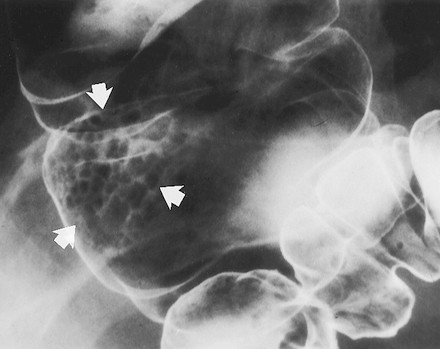

Các khối u tuyến lông nhung có thể là các tổn thương chia thùy, phẳng, còn gọi là các tổn thương hình “tấm thảm”, chúng được mô tả là các thay đổi tinh vi ở bề mặt đại tràng, lồi rất ít hoặc không lồi vào lòng đại tràng. Kích thước trung bình của u 4 x 6 cm, thường mọc ở trực tràng, manh tràng, và đại tràng lên. Trên phim cản quang kép nhìn thẳng, các nốt to, nhỏ tụ với nhau thành mảng, phân cách nhau bởi các lưới mảnh đọng baryt (Hình 8) [5]. Khi nhìn nghiêng, tổn thương có bờ không đều, trái với bờ nhẵn của niêm mạc bình thường bao quanh.

Hình 8. Hình cản quang kép chếch sau phải bộc lộ một tổn thương hình thảm. Chú ý bề mặt hình lưới-nốt của tổn thương (mũi tên) ở manh tràng do baryt lấp đầy các kẽ hở của khối u tuyến lông nhung.